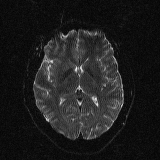

Refer to caption

(a) b = 0 s/mm2

(b) b = 1000 s/mm2

(c) b = 4000 s/mm2

(d) b = 0 s/mm2

(e) b = 1000 s/mm2

(f) b = 4000 s/mm2

Figure 4: Example axial slice from synthetic brain DTI. Noiseless reference (top) and noisy images with σ=7%𝜎percent7\sigma=7\%italic_σ = 7 % of the true white matter intensity at b=0 (bottom) are shown. Several differently shaped lesions are visible, with f=0.75𝑓0.75f=0.75italic_f = 0.75, D1=400mm2ssubscript𝐷1400𝑚superscript𝑚2𝑠D_{1}=400\frac{mm^{2}}{s}italic_D start_POSTSUBSCRIPT 1 end_POSTSUBSCRIPT = 400 divide start_ARG italic_m italic_m start_POSTSUPERSCRIPT 2 end_POSTSUPERSCRIPT end_ARG start_ARG italic_s end_ARG, D2=600mm2ssubscript𝐷2600𝑚superscript𝑚2𝑠D_{2}=600\frac{mm^{2}}{s}italic_D start_POSTSUBSCRIPT 2 end_POSTSUBSCRIPT = 600 divide start_ARG italic_m italic_m start_POSTSUPERSCRIPT 2 end_POSTSUPERSCRIPT end_ARG start_ARG italic_s end_ARG, ΔT2=15Δsubscript𝑇215\Delta T_{2}=15roman_Δ italic_T start_POSTSUBSCRIPT 2 end_POSTSUBSCRIPT = 15 ms. They are hyperintense at all b-values compared to normal white matter. Exponential SNR drop is well visible for the b4000 image.

Parameters ρ𝜌\rhoitalic_ρ, T1subscript𝑇1T_{1}italic_T start_POSTSUBSCRIPT 1 end_POSTSUBSCRIPT and T2subscript𝑇2T_{2}italic_T start_POSTSUBSCRIPT 2 end_POSTSUBSCRIPT for lesions were equal to white matter values. D1subscript𝐷1D_{1}italic_D start_POSTSUBSCRIPT 1 end_POSTSUBSCRIPT and D2subscript𝐷2D_{2}italic_D start_POSTSUBSCRIPT 2 end_POSTSUBSCRIPT were sampled uniformly from the interval [0.3,1.35), f𝑓fitalic_f from the interval [0,1] and ΔT2Δsubscript𝑇2\Delta T_{2}roman_Δ italic_T start_POSTSUBSCRIPT 2 end_POSTSUBSCRIPT from the interval [-30,30] ms with a step of 5 ms. The latter was used to incorporate lesions visible in b0 images, both hyper- and hypointense. A slice with hyperintense lesions in a noiseless and noisy case is shown in Figure 4.